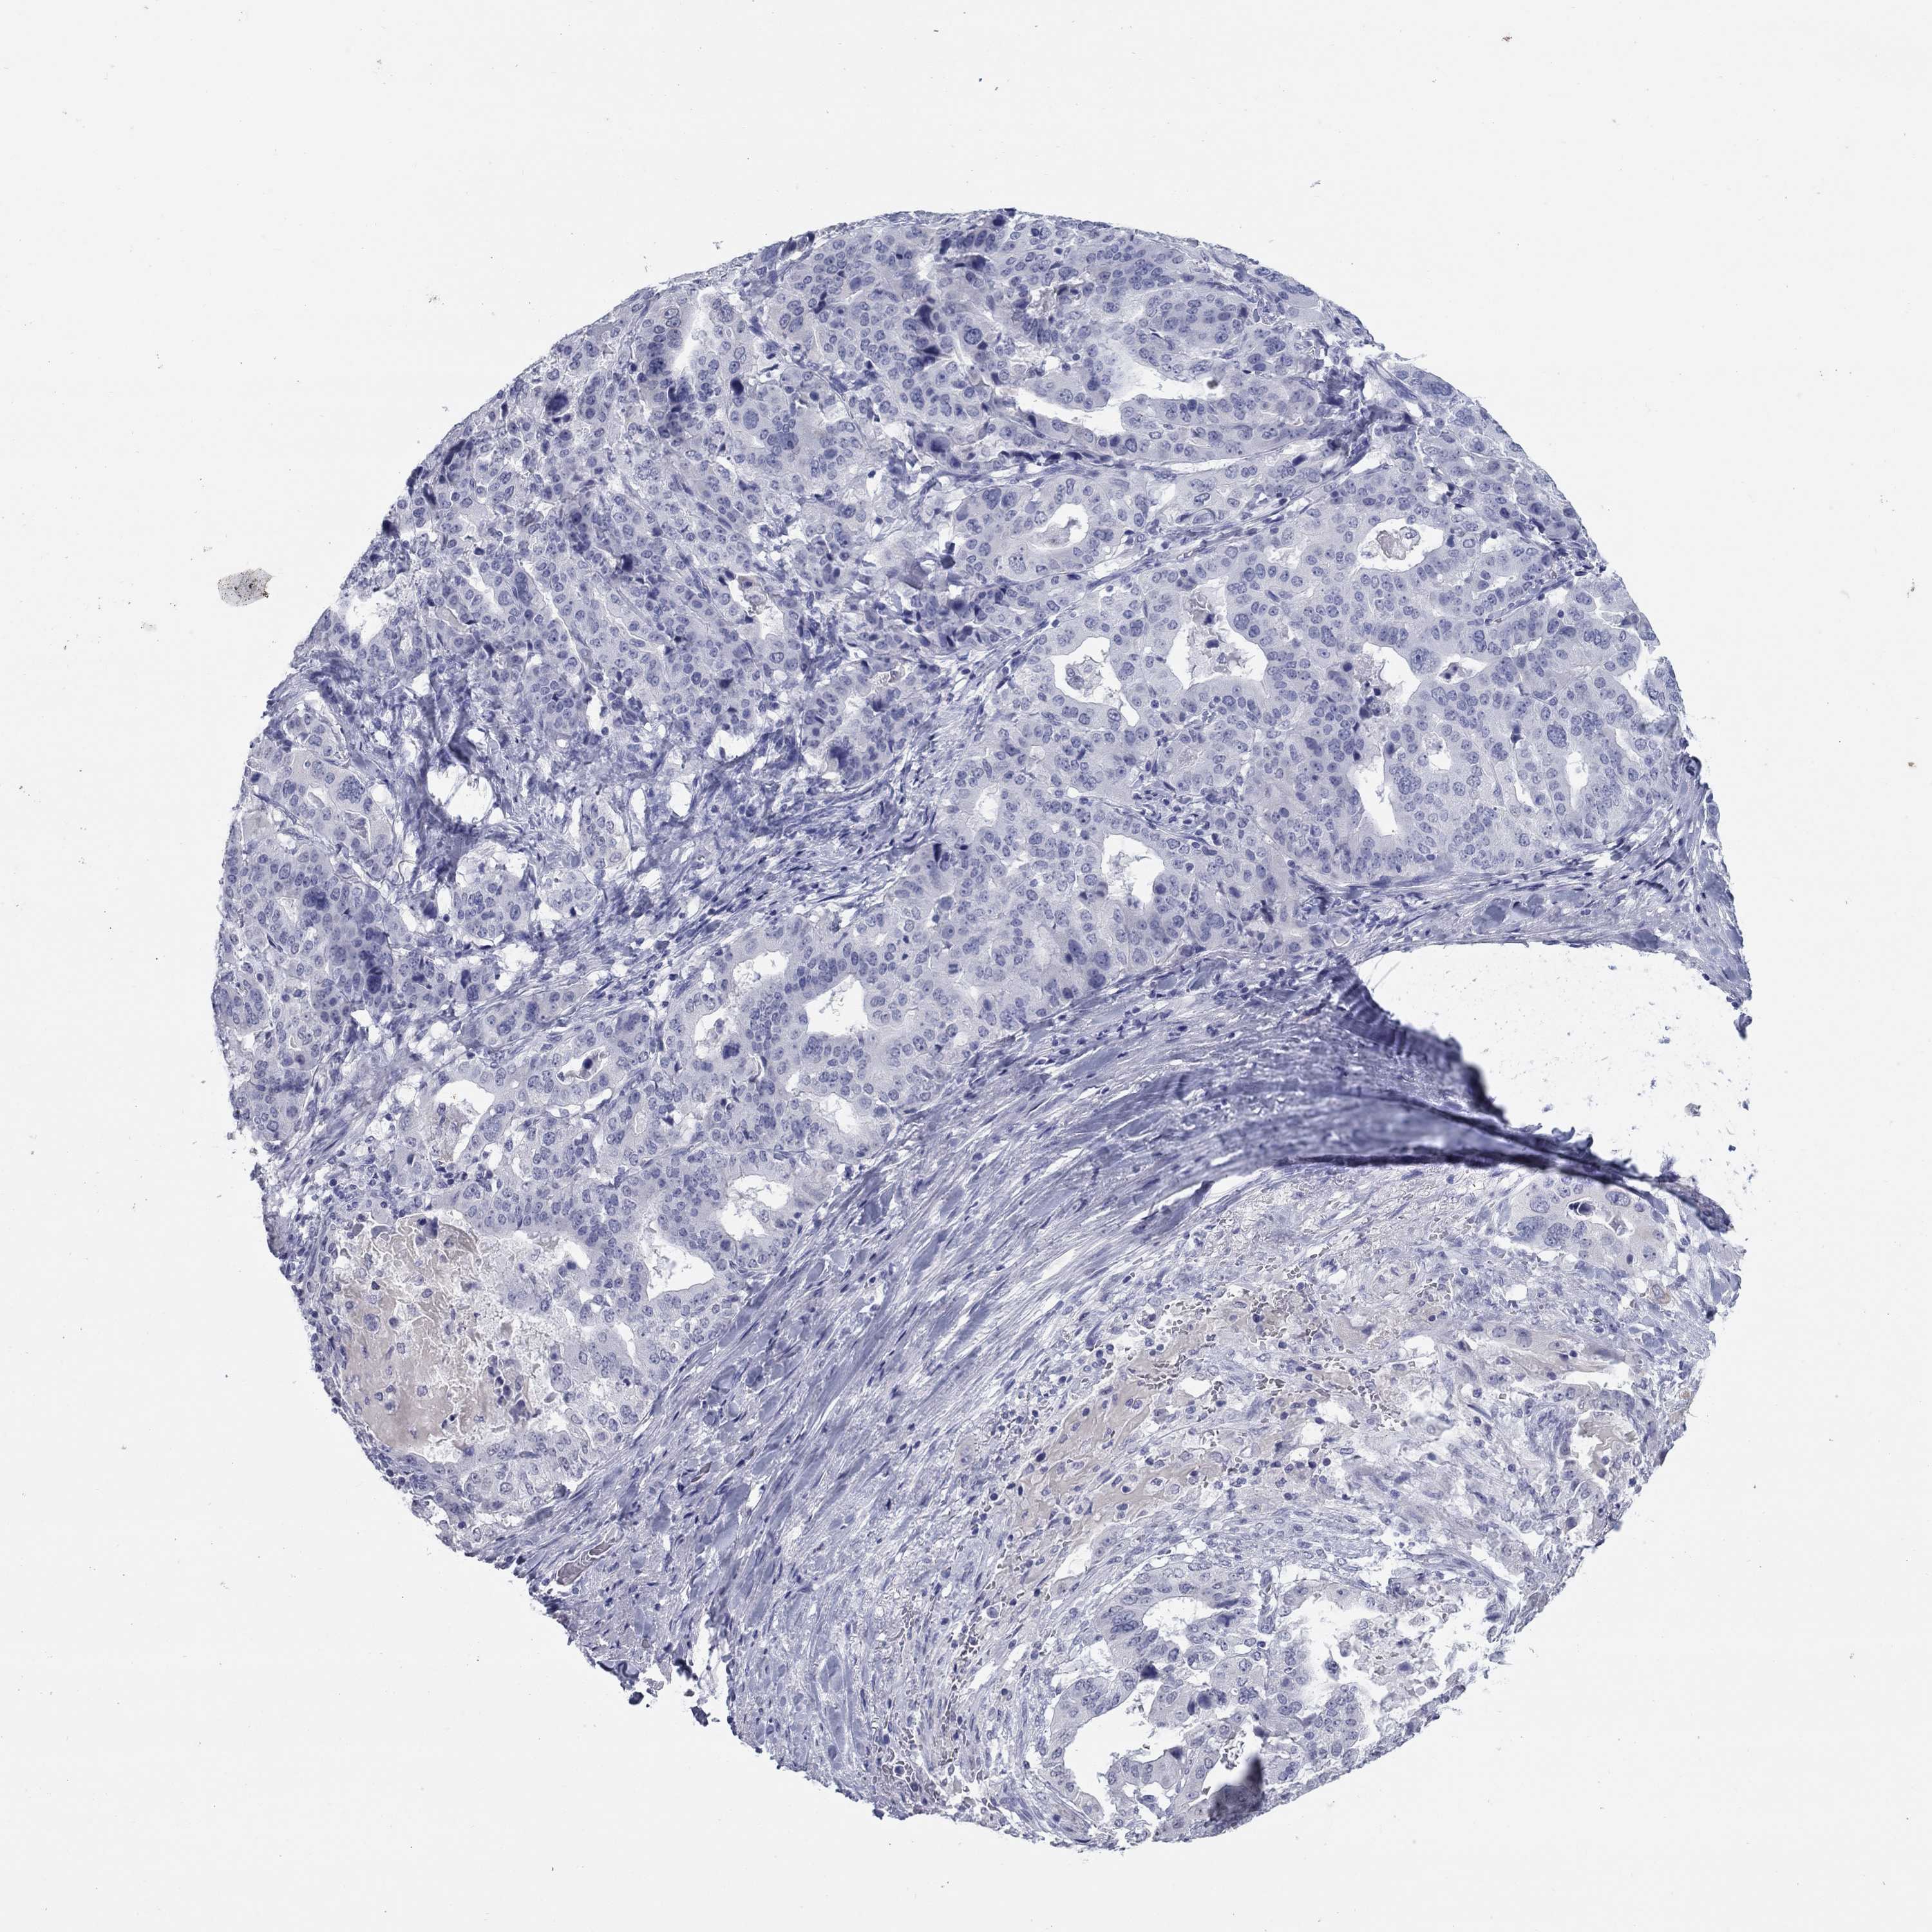

STOMACH CANCER - Protein expressioni

A mouse-over function shows sample information and annotation data. Click on an image to view it in a full screen mode. Samples can be filtered based on level of antibody staining by selecting one or several of the following categories: high, medium, low and not detected. The assay and annotation is described here.

Note that samples used for immunohistochemistry by the Human Protein Atlas do not correspond to samples in the TCGA dataset.

Antibody stainingi

Antibody staining in the annotated cell types in the current human tissue is reported as not detected, low, medium, or high, based on conventional immunohistochemistry profiling in selected tissues. This score is based on the combination of the staining intensity and fraction of stained cells.

Each image is clickable and will lead to virtual microscopy that enables deeper exploration of all samples and also displays staining intensity scores, fraction scores and subcellular localization as well as patient and tissue information for each sample.

Antibody HPA019367

Antibody HPA076201

Staining

High

Medium

Low

Not detected

Intensity

Strong

Moderate

Weak

Negative

Quantity

>75%

75%-25%

<25%

None

Location

Nuclear

Cytoplasmic/membranous

Cytoplasmic/membranous,nuclear

Adenocarcinoma, NOS

Adenocarcinoma, High grade